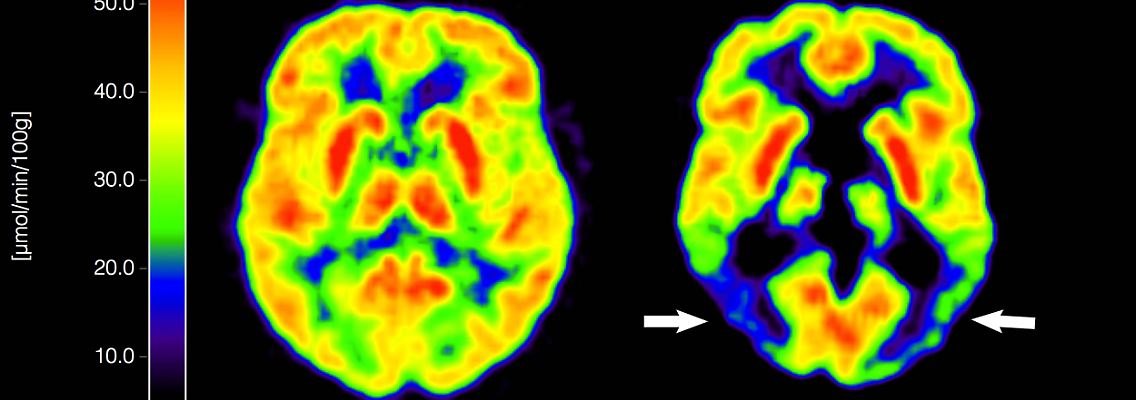

(Foto: IMAGO/USA TODAY Network)

Es gibt allerdings noch eine weitere Einschränkung: Das Mittel soll nur an jene Alzheimer-Patienten verabreicht werden, die lediglich eine oder keine Kopie von ApoE4 haben. Bei dem Gen handelt es sich um eine Variante des Gens für das Protein Apolipoprotein E. Bei ihnen ist die Wahrscheinlichkeit für bestimmte Nebenwirkungen - Schwellungen und Blutungen im Gehirn - geringer als bei Menschen mit zwei ApoE4-Kopien. Menschen mit nur einer oder keiner ApoE4-Kopie machen dem DZNE zufolge in Deutschland etwa 80 Prozent der Alzheimer-Patienten aus.

Aufgrund der Nebenwirkungen wie Schwellungen und Mikroblutungen im Gehirn war Lecanemab bei einer ersten Prüfung der EU-Arzneimittelbehörde EMA noch abgelehnt worden. Bei einer erneuten Prüfung kamen die Behörden jedoch zu dem Schluss, dass für die erwähnte Untergruppe der Alzheimer-Patienten der Nutzen die Risiken übersteige.